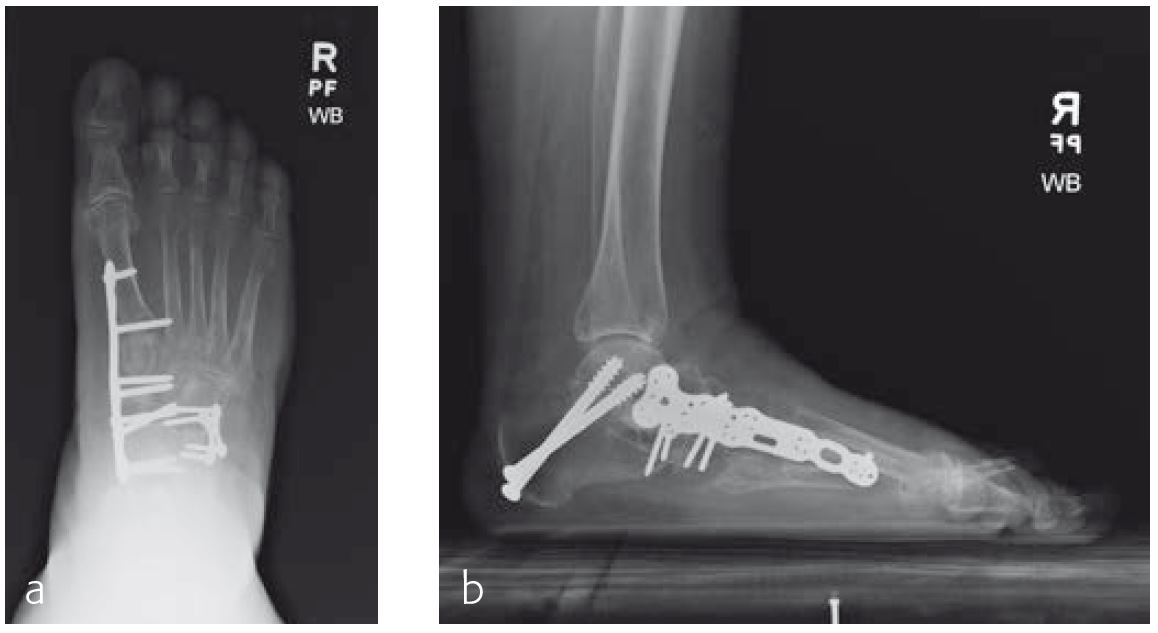

A 70-year-old female patient (Fig 1) had a long history of increasing painful deformity of her foot. She also noted increasing gait problems. There was no history of initial trauma. The examination showed severe rigid flatfoot deformity.

An extended triple arthrodesis was performed. Medially, the new Medial Column Plate was used, securing the talonavicular, naviculocuneiform, and tarsometatarsal joints (Fig 2). The X-plate is lateral and secured the calcaneo-cuboid joint. Two 7.3 mm screws were used to secure the subtalar joint.